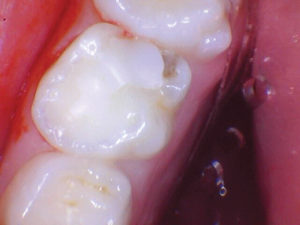

Caso 1

Un paciente de 8 años presentó descomposición de OD en un primer molar primario con síntomas de pulpitis reversible. El diente fue el tratamiento planificado para una restauración de OD con Activa Bioactive Restorative (Pulpdent). Tras la excavación por descomposición, se produjo una exposición pulpar que requirió una pulpotomía terapéutica. Debido a la edad del paciente, me sentí cómodo con una pulpotomía terapéutica con Biodentine (Septodont) seguida de una restauración estética. Si el paciente hubiera tenido entre cuatro y cinco años, me habría restaurado con una corona de acero inoxidable debido a su historial comprobado de longevidad.

Figura 1 Vista preoperatoria del primer molar primario superior. |